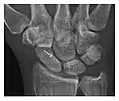

- a

- b

Figure 14: Subcapital insufficiency fracture in a 55-year-old man with a left hip pain without a history of trauma. Anteroposterior and Lauenstein view radiographs centered on the left hip do not show an obvious fracture line, but mild acetabular osteophytosis was noted consistent with hip osteoarthritis (not shown). (a) Coronal T1-weighted MRI shows a linear low-signal band through the femoral neck corresponding to a fracture line (arrowheads). (b) Bone scintigraphy shows focal uptake (arrow) corresponding to the fracture.[1]